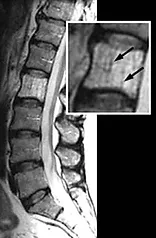

Магнитно-резонансная томография высоко информативна в отношении гемангиом позвонков и рассматриватся как вспомогательный метод диагностики. Типичная МР-картина гемангиом позвонков характеризуется неоднородным сигналом на Т1- и Т2-взвешенных изображениях (ВИ). Этот паттерн представлен множественными зонами как высокого, так и низкого по интенсивности сигнала, что вызывает картину «испещрённости». При этом области низкого или изоинтенсивного сигнала как на Т1 так и Т2 ВИ соответствуют костные трабекулы, а иногда сосудистые полости («симптом пустоты потока»). Гиперинтенсивный сигнал в Т1 и Т2 ВИ присущ жировой ткани. Количество жира в структуре гемангиомы обратно пропорционально степени её опухолевой активности. Гемангиомы с высоким содержанием жировой ткани чаще бессимптомны и не характеризуются активным ростом. Округлые или бесформенные, различных размеров жировые включения в телах позвонков, не имеющие симптома «испещрённости» - не являются истинными гемангиомами и должны описываться как очаги липоангиоматоза. Липоангиоматозные образования, относятся к дегенеративной патологии позвоночника, являются следствием адипозной инволюции красного костного мозга и не имеют клинического значения. Очаги липоангиоматоза почти всегда небольших размеров, визуализируются сразу во многих позвонках, могут быть множественными в пределах одного тела позвонка, склонны к слиянию и не имеют специфичных для гемангиом рентгенологических симптомов. Для гемангиом характеризующихся активным ростом, выраженными клиническими проявлениями характерен неоднородный изо-гипоинтенсивный сигнал в Т1 ВИ и 7 гиперинтенсивный сигнал в Т2 ВИ (сигнал жидкости). При этом в режиме жироподавления отмечается резкое увеличение интенсивности сигнала от гемангиомы.